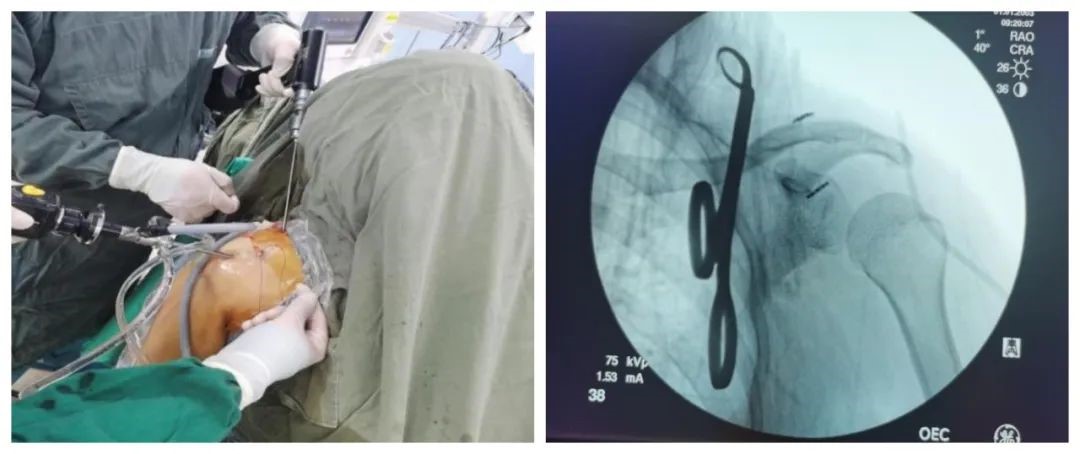

术中情况 复位情况

今年54岁的董阿姨,骑车时摔伤自己的左肩后,出现肿胀、疼痛,并且活动受限,于是来到我院关节外科就诊。刘飞主任医师仔细询问病史,认真查体,发现患者受伤部分的皮肤表面可见一隆起。左肩正侧位X线检查提示:肩锁关节脱位。患者住院后,刘飞主任为其进行了“关节镜下带袢纽扣肩锁关节固定术”,术后根据其个体情况制定了相应的康复计划。前几天,董阿姨来院复查,对手术结果十分满意。她说:孩子在网上查了很多资料,听说手术时要用钢板固定,后期还要再做手术把钢板取出来。而刘飞主任给我做的微创手术只有几个小伤口,恢复的很快,最重要的是不需要再次手术,真好!